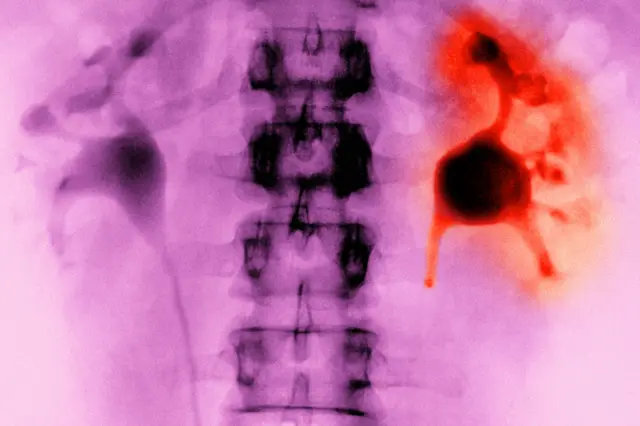

Indonesia melarang jual-beli organ tubuh manusia seperti diatur dalam Undang Undang Kesehatan maupun KUHP, “Organ dan/atau jaringan tubuh dilarang diperjualbelikan dengan dalih apapun”.

Keberadaan sindikat perdagangan organ tubuh manusia, khususnya ginjal akan terus ada selama terdapat permintaan. Sejauh ini di Indonesia, tidak ada wadah resmi donor ginjal seperti halnya donor darah.

Wakil Ketua Umum Pengurus Besar Ikatan Dokter Indonesia (IDI), Mahesa Pranadipa Maikel mengatakan transplantasi organ tubuh manusia diperbolehkan selama mengikuti prosedur dan aturan hukum yang berlaku.

Peraturan tentang syarat transplantasi organ tubuh ini dijelaskan secara rinci melalui Peraturan Pemerintah No.53 tahun 2021 tentang Transplantasi Organ dan Jaringan.

Salah satunya dijelaskan, seluruh operasi transplantasi dilakukan di rumah sakit yang ditunjuk oleh menteri kesehatan.

Dalam aturan itu juga disebutkan sejumlah syarat bagi orang yang ingin memberikan organ tubuhnya kepada orang lain secara sukarela. Berusia paling muda 18 tahun, membuat pernyataan tertulis menyumbangkan organ tubuh tanpa imbalan, mendapat persetujuan orang terdekat, dan mengetahui risiko pascaoperasi.